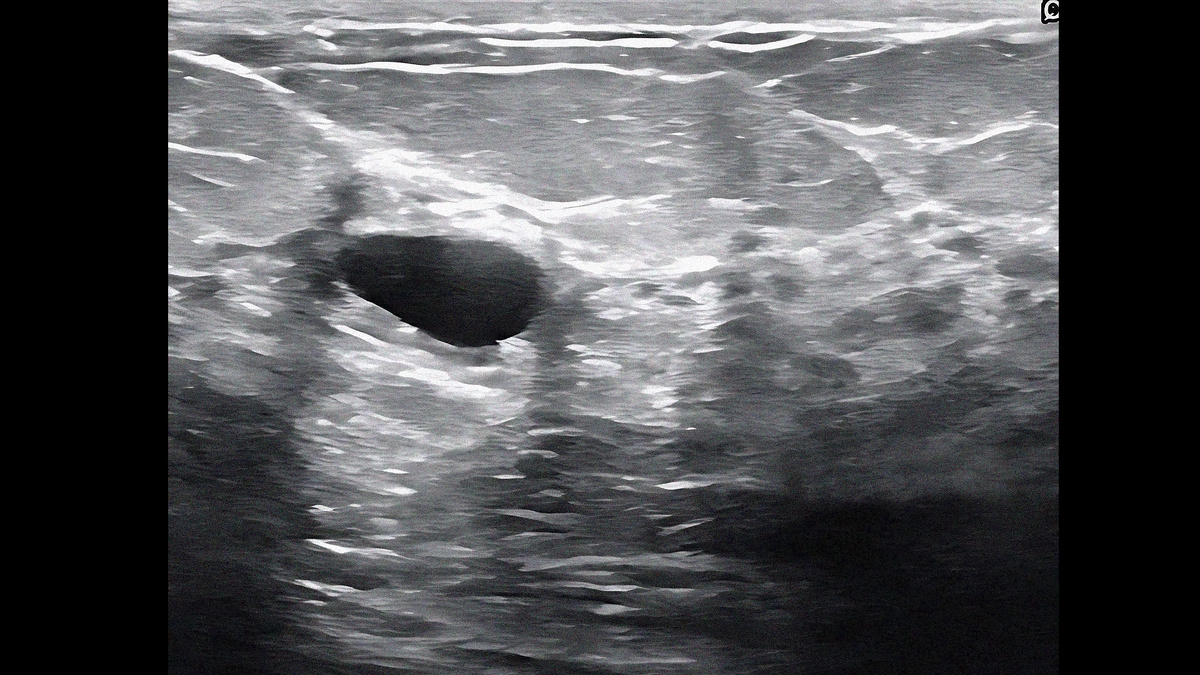

Простая киста молочной железы